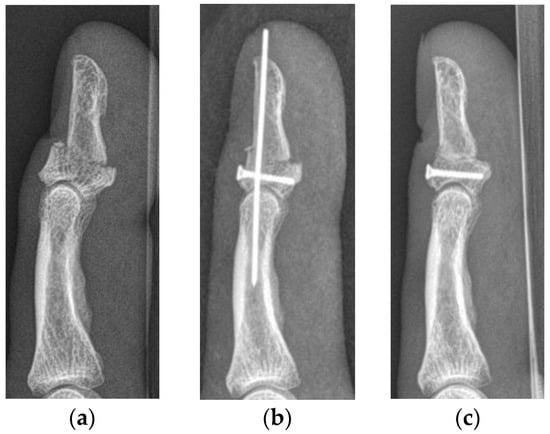

Figure 4. Lateral radiographs of a type Vb jersey finger, with severe displacement of the bony fragments and a resulting articular step-off (a). The same patient after surgical refixation using a mini-cortical screw and a K-wire (b). Lateral radiographs after K-wire removal 6 weeks after surgery (c). The functional outcome of this patient was classified as good.

The median primary bony displacement in patients with SD injuries was 5.8 mm (1.2–6.3 mm) and the median articular step-off 2.5 mm (0.9–3.9 mm). The functional outcome in cases who subsequently underwent surgery was poor in two and good in one patient. The patients with a poor outcome developed osteoarthritis grade 4 according to the Kellgren–Lawrence Score within 6 months, resulting in complete stiffness of the DIP joint. Their injuries were reconstructed with the help of a Bunnell pull-out suture and a K-wire in one patient and with three K-wires in the other. The patient receiving reconstruction with the Bunnell pull-out suture lost the ulnar part of his nail due to the refixation. The patient with a good outcome received reconstruction with a mini-cortical screw and a K-wire (Figure 4).

In the case series of Al-Quattan [6], who was the first to describe jersey finger type V, all operated cases reached an almost unimpaired ROM after treatment without concomitant complications. The reconstruction of type Va was performed using only one 3–0 polypropylene pull-out suture; in cases of type Vb injuries, K-wires for DIP joint stabilization were added. Although we used the same technique for reconstruction in some patients, the achieved results were not as favorable. We also encountered one case with postoperative nail deformity, as this is a common complication when using pull-out sutures for reconstruction. The patient receiving reconstruction with three K-wires showed a worse radiological outcome, resulting in joint stiffness after a postoperative period of 4 months. Although this method of refixation showed sufficient results in the treatment of jersey finger type III injuries [17], it seems inappropriate for jersey finger type V injuries. Another fateful outcome was observed in the type Vb injury reconstructed with a Bunnell pull-out suture and one K-wire, resulting in severe osteoarthritis after 6 months. Refixations with these techniques seem to treat these severe injuries insufficiently.